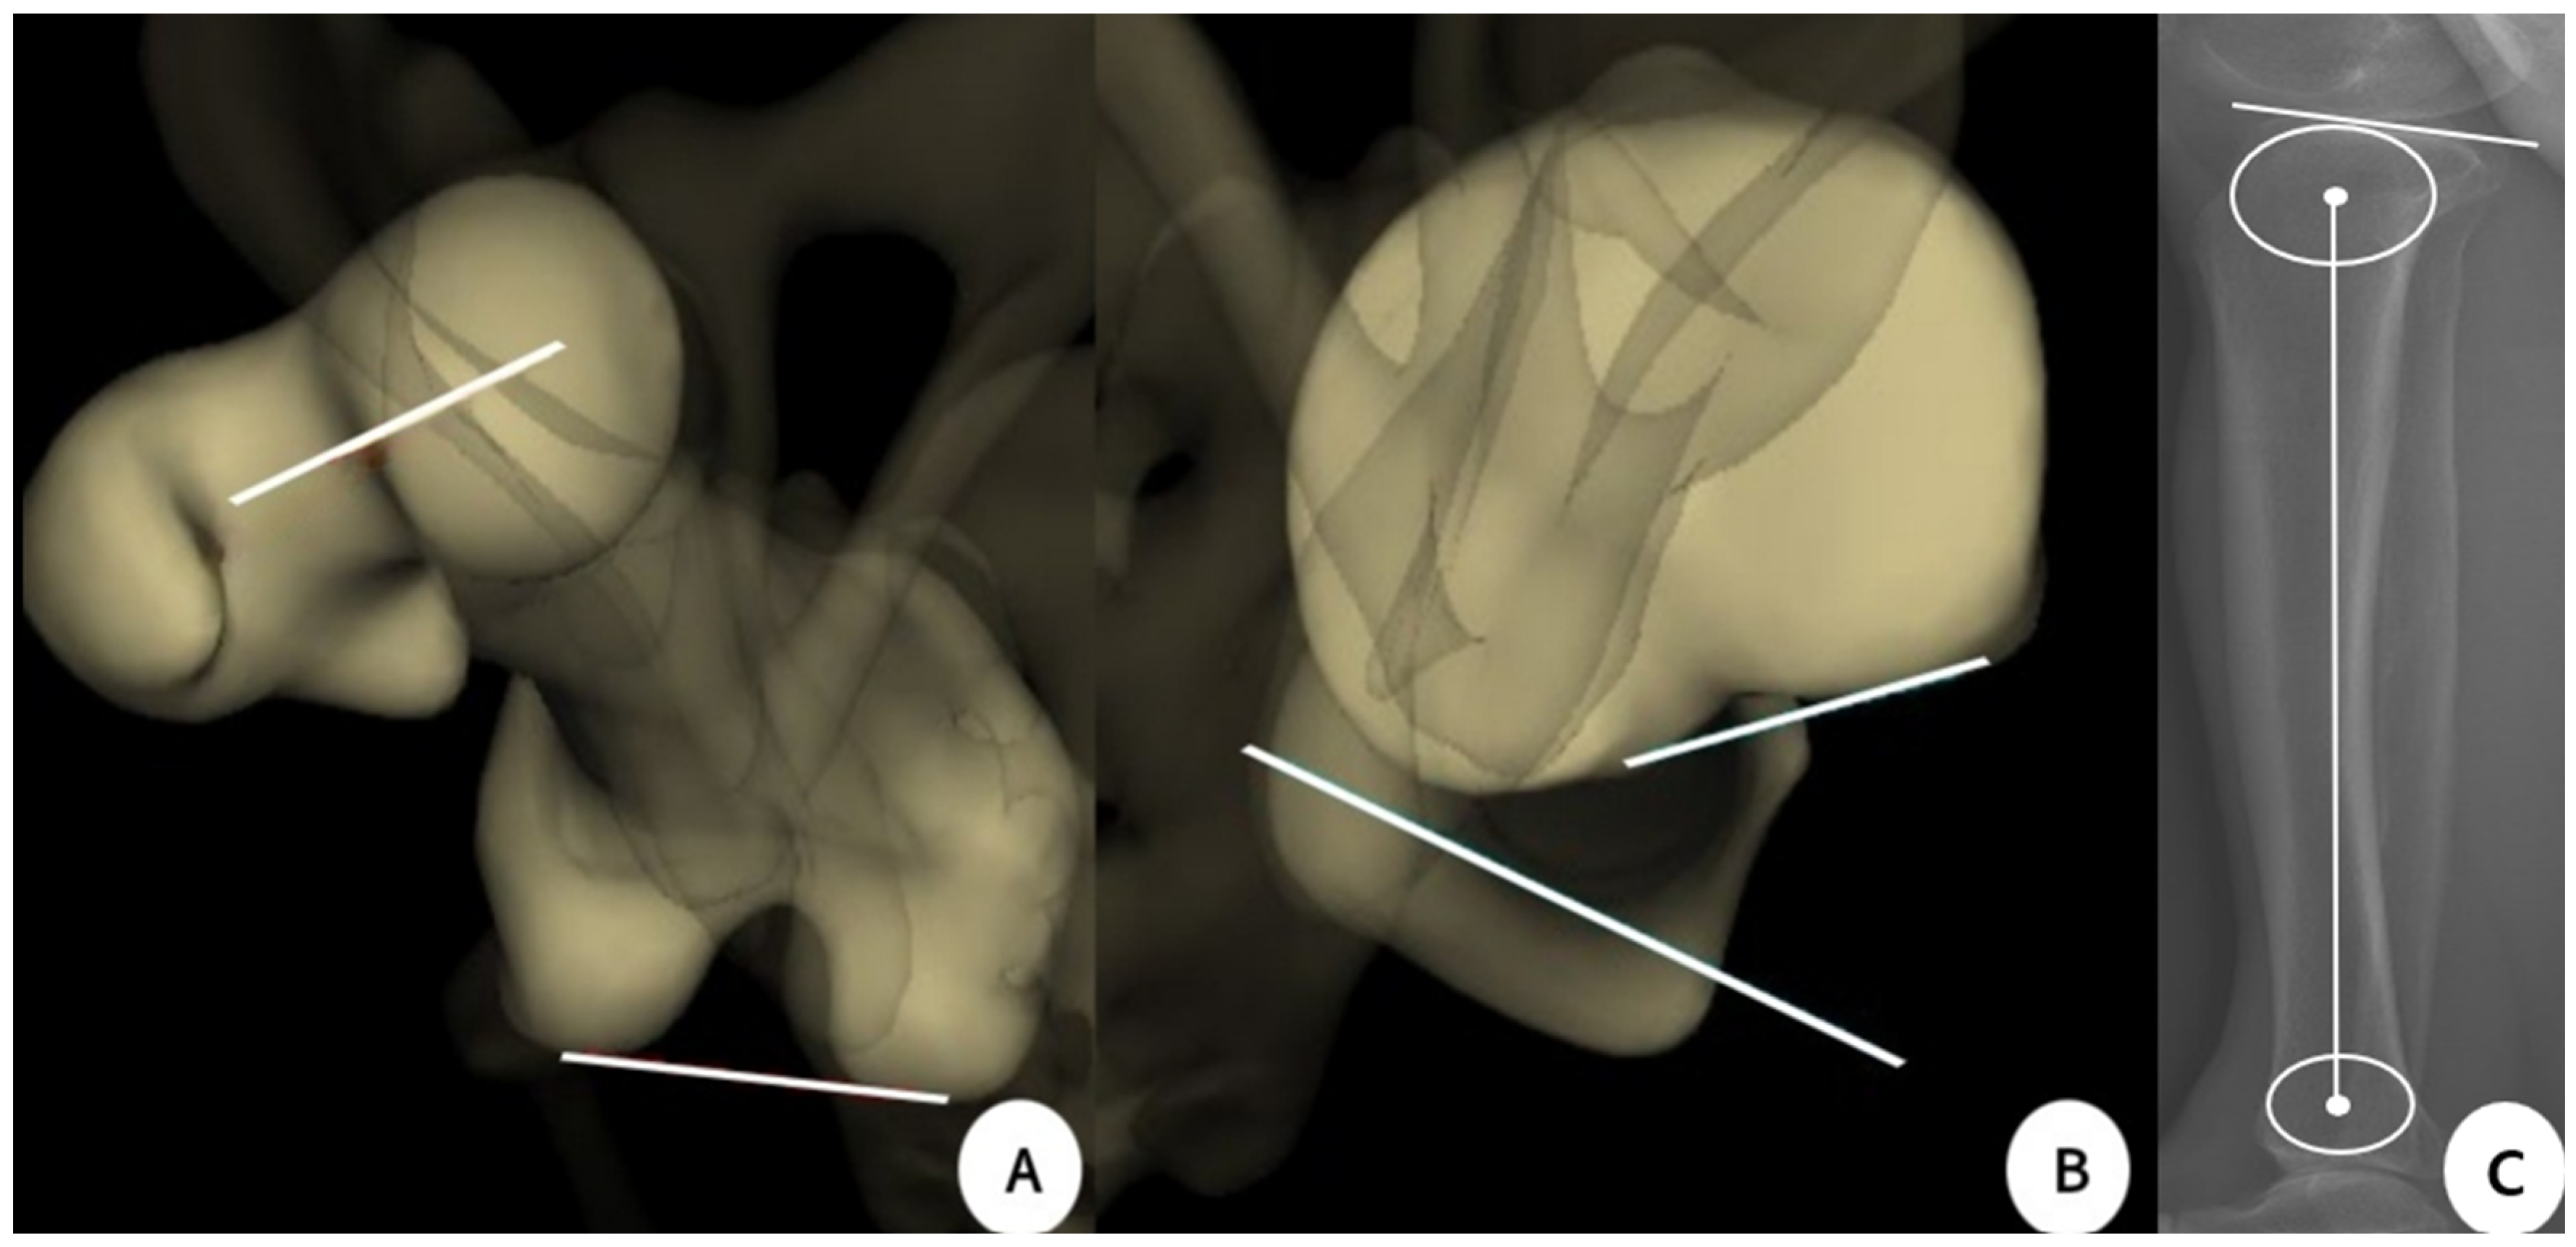

2.2. Evaluation Methods

2.3. Measurement of Parameters and Clinical Outcomes